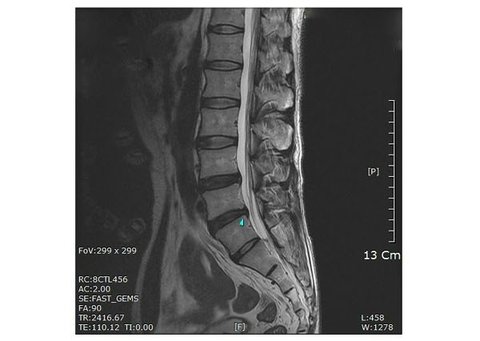

무소속 강용석 의원이 공개한 박원순 아들, 박주신의 MRI 사진이라고 하는데요.

이 사진을 제출하고 허리디스크 4급판정을 받았다고 합니다.

하지만 신경외과 척추 전문의는 이 사진이 '고도비만 환자의 MRI' 사진이라고 했어요.

그 이유인 즉슨, 이 사진으로는 일단 동영상처럼 '정상적인 활동' 을 할 수 없으며, 최소 피하지방의 두께가 35~45mm 정도로 추정되며 외형적으로 비만으로 느끼기에 충분하다고 할 수 있는 사진, 이라고 했습니다.

▲ 키 173cm, 몸무게 63kg의 체격을 지닌 디스크 환자의 MRI 사진.

박원순 시장의 아들, 박주신의 체격은 173cm에 63kg으로 알려져있다고 합니다.